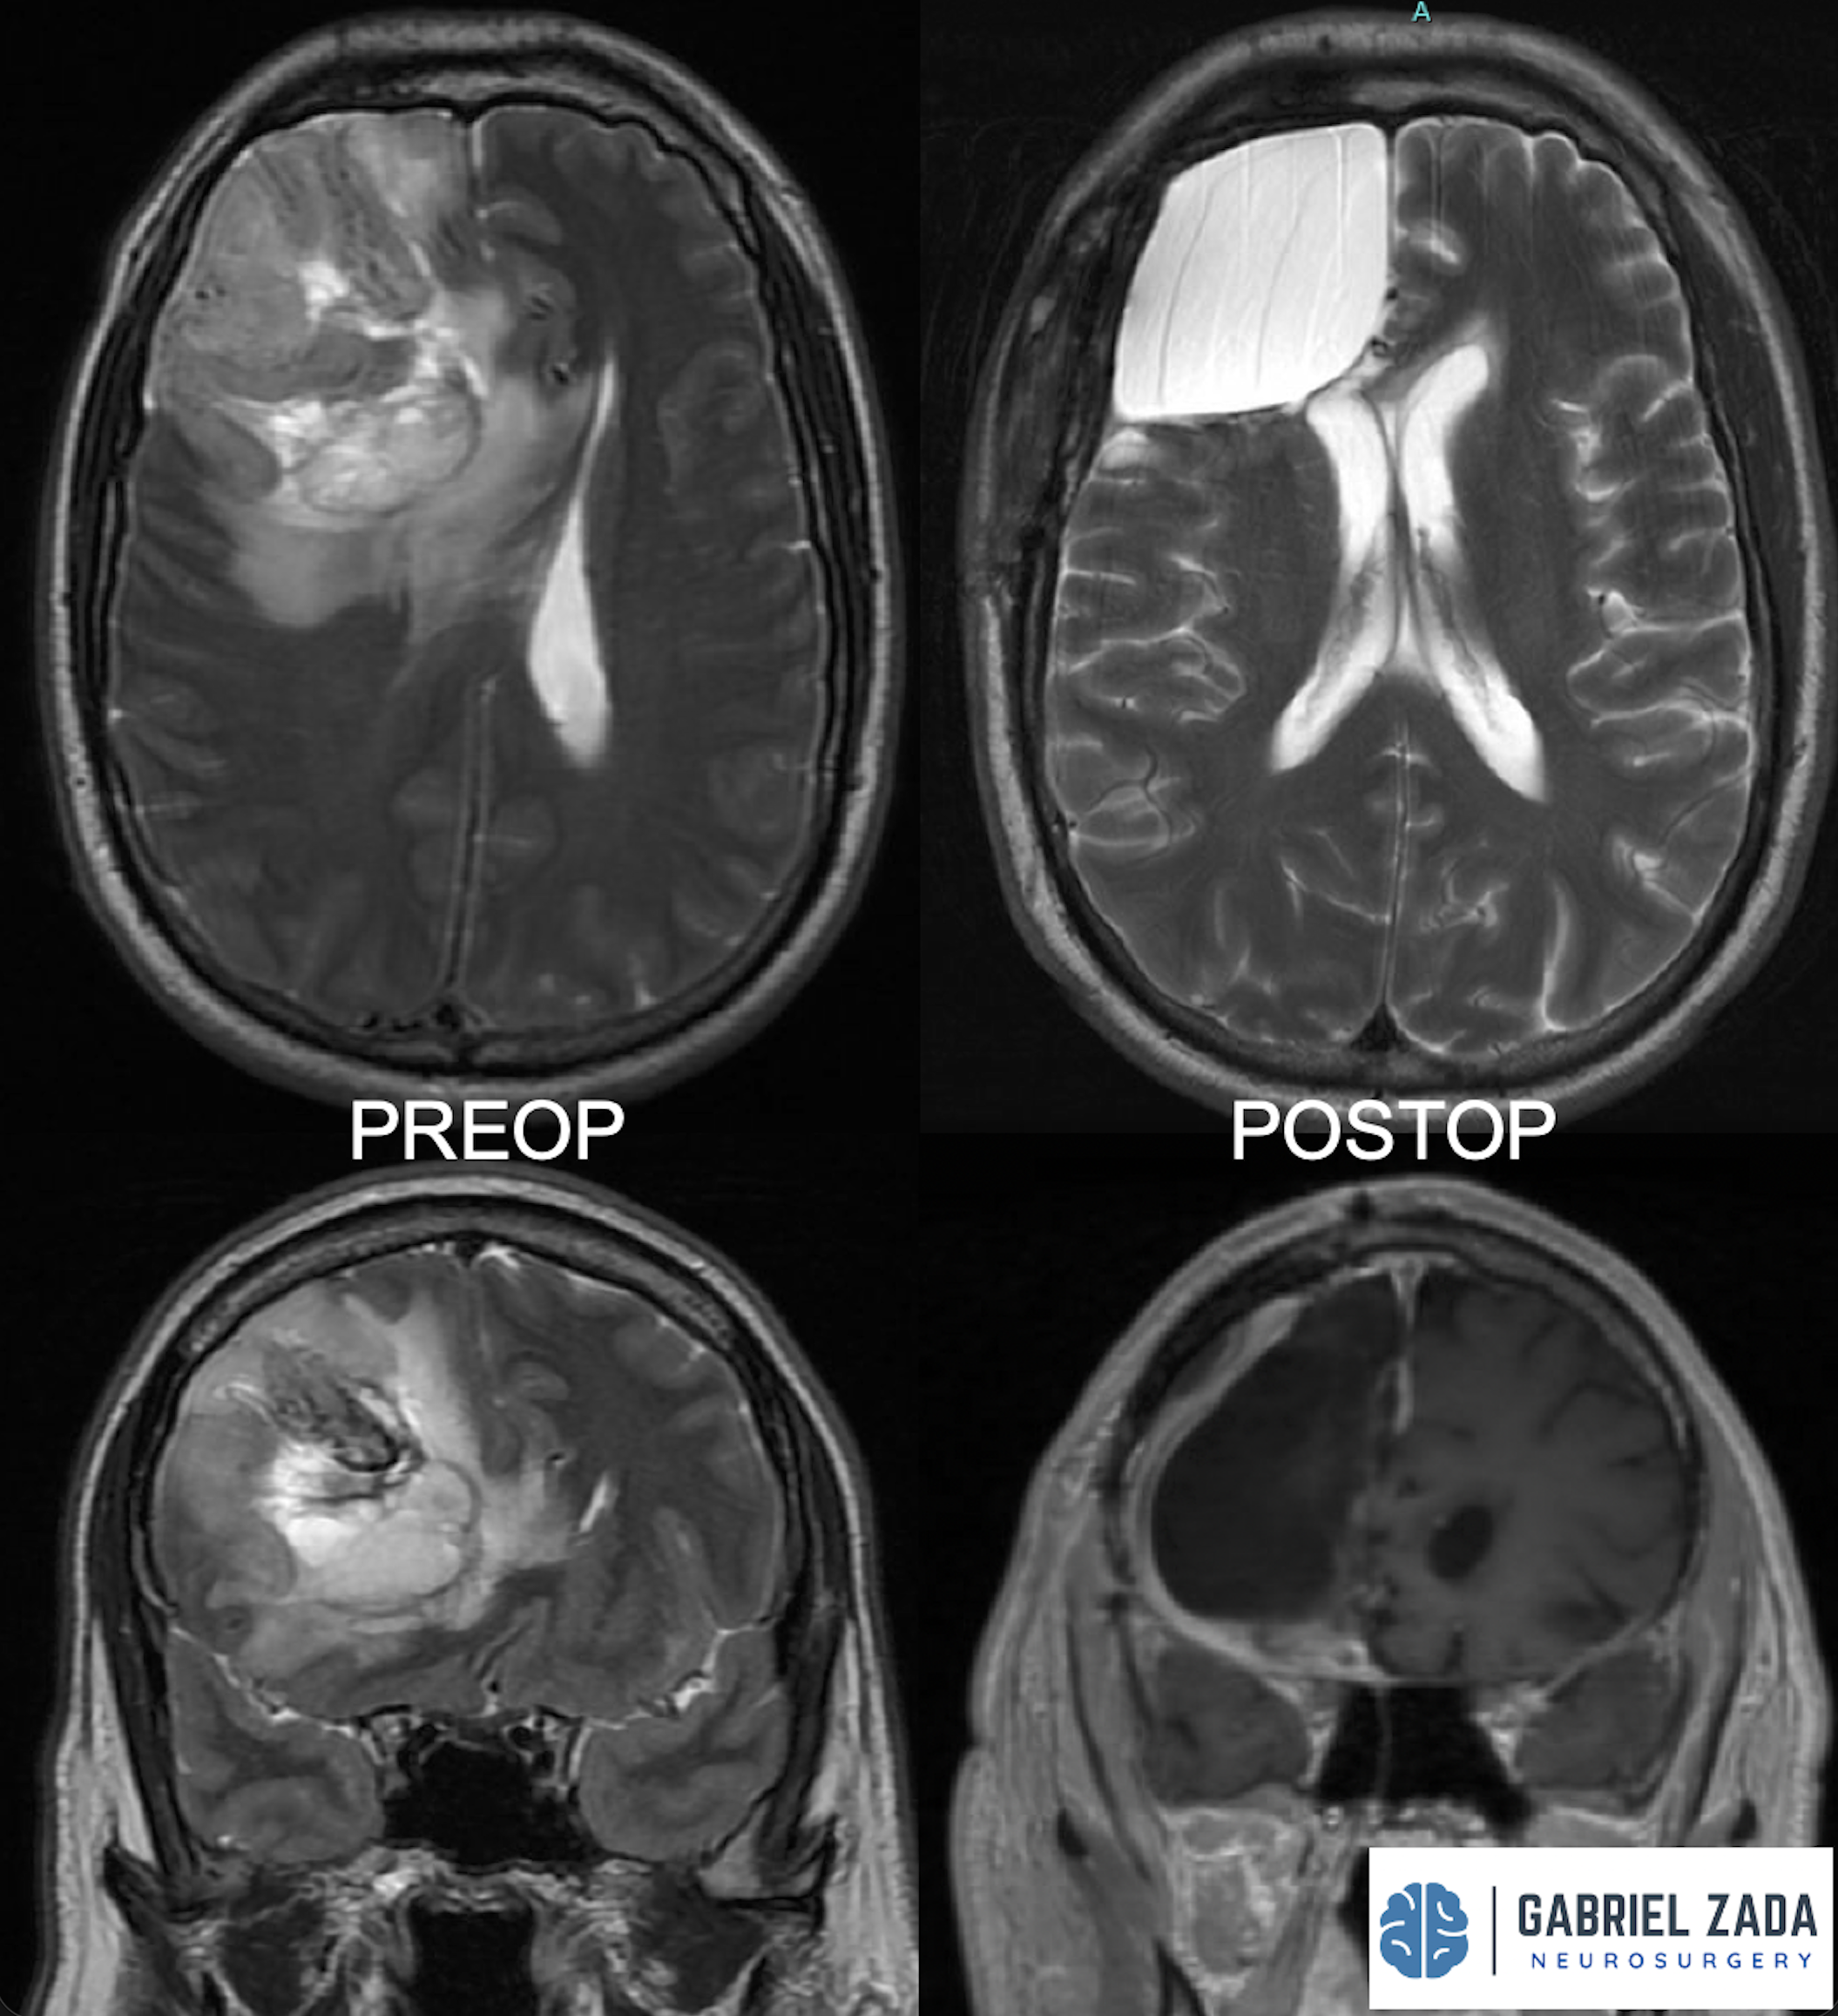

Explore this comprehensive gallery featuring pre‑ and post‑operative imaging of patients with skull‑base tumors treated by Gabriel Zada, MD, MS, FAANS, FACS. These cases highlight Dr. Zada’s expertise in advanced neurosurgical techniques and outcomes.

*Representative cases shown for educational purposes. All images de-identified. Individual results vary.